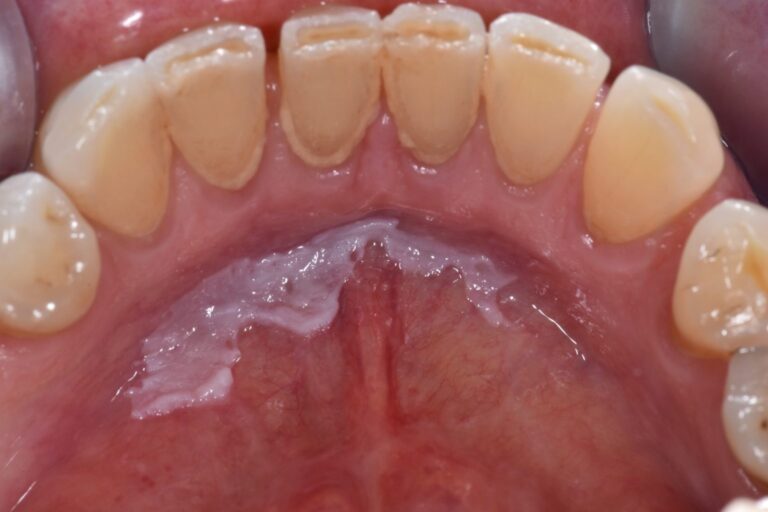

Czym jest elektrokoagulacja? Elektrokoagulacja to zabieg polegający na kontrolowanym wykorzystaniu prądu elektrycznego w celu zamknięcia naczyń krwionośnych oraz usunięcia zmienionych tkanek. W stomatologii metoda ta znajduje zastosowanie przede wszystkim w chirurgii i periodontologii. Stomatolog w nowoczesnej klinika stomatologiczna Kraków wykorzystuje…